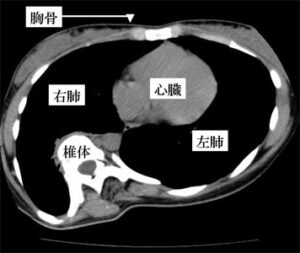

手術の目的は、そのカーブの進行を止めることです。重度の側弯症になった場合(約80度以上)、肺機能の低下が生じます。脊柱カーブによって胸郭が変形するからです。(図1参照)